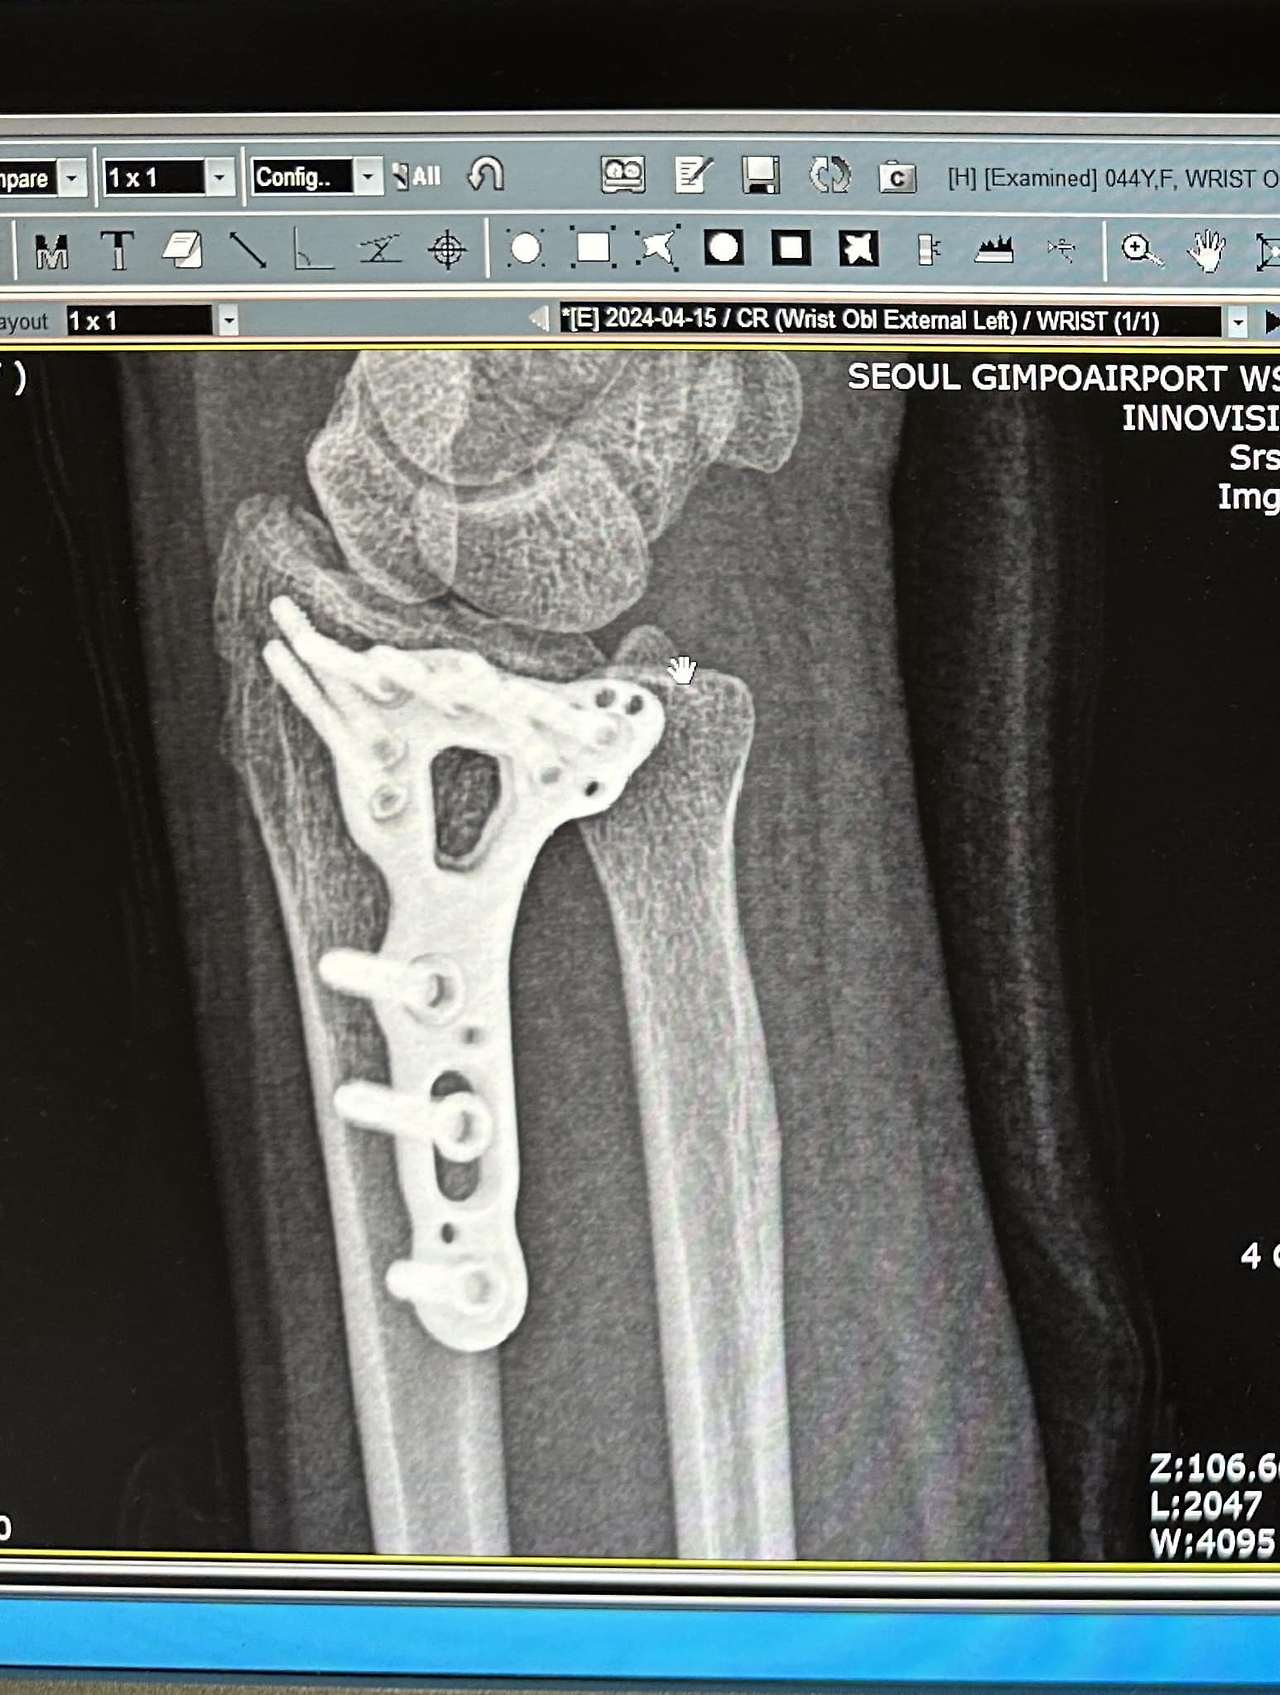

2. 어제 실밥 뽑으러 가서 팔뚝에 박은 거 뭐냐고 물어봤더니 티타늄이라고 하심 ㅋㅋㅋ 컴퓨터 모니터 최신 방은 사진 좀 찍어도 되냐고 하니까 3초 동안 쳐다보다가 그냥 찍으라고 하셨음 ㅋㅋㅋ 사이보그 된 거 같고 좋다. 미리 인공지능 로봇 셀프 체험 ㅋㅋㅋ 약간 시니어 체험 같기도 합니다 독수리 타자도 치고…